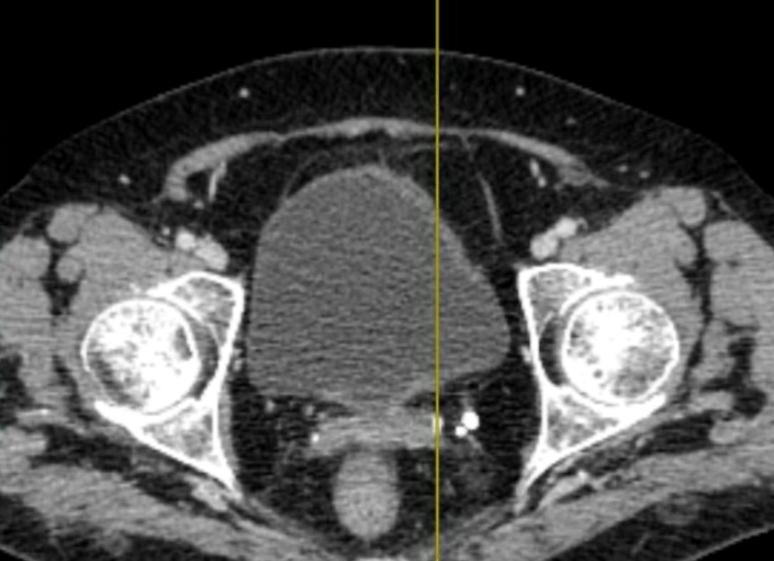

Наиболее выраженные инволютивные процессы после менопаузы происходят именно во внутренних половых органах женщины. Матка является органом-мишенью для половых гормонов, и в связи с возникающей после менопаузы гипоэстрогенией теряет около 35 % своего объёма,  что связано с развитием атрофических процессов в ее тканях. Контролировать изменения, происходящие во внутренних половых органах женщины, на сегодняшний день можно с помощью новых эффективных методов исследований, таких как ультразвуковое исследование, допплерография, гидросонография, гистероскопия, магнитно-резонансная томография и так далее. С помощью этих методов можно изучить все инволютивные изменения в матке и яичниках на протяжении всего постменопаузального периода.

Наиболее выражены атрофические процессы в нем во время первых 2-5 лет после менопаузы. Эхогенность миометрия в первые годы после менопаузы средняя, и возрастает она с увеличением продолжительности постменопаузального периода. Наблюдаются фиброзные изменения в миометрии в виде возникновения множественные гиперэхогенных участков в нем. По данным допплеровского исследования регистрируется значительное обеднение кровотока в периферических слоях миометрия. В то же время, если у женщины до менопаузы наблюдались миоматозные узлы, они также подвергаются инволюции после менопаузы.

Как изменения гормонального фона после менопаузы отражаются на яичниках

Изменения гормонального фона после менопаузы отражаются также на структуре самих яичников. В постменопаузе значительно уменьшается их объём и размеры, наблюдаются также изменения эхоструктуры яичников. Выделяют два основных типа постменопаузальных изменений в яичниках:

• при изменениях атрофического типа – наблюдается значительно уменьшение объёма и размеров яичников;

• при изменениях гиперпластического типа – размеры яичников уменьшаются постепенно и достаточно медленно, возможно образование мелких жидкостных включений в них.